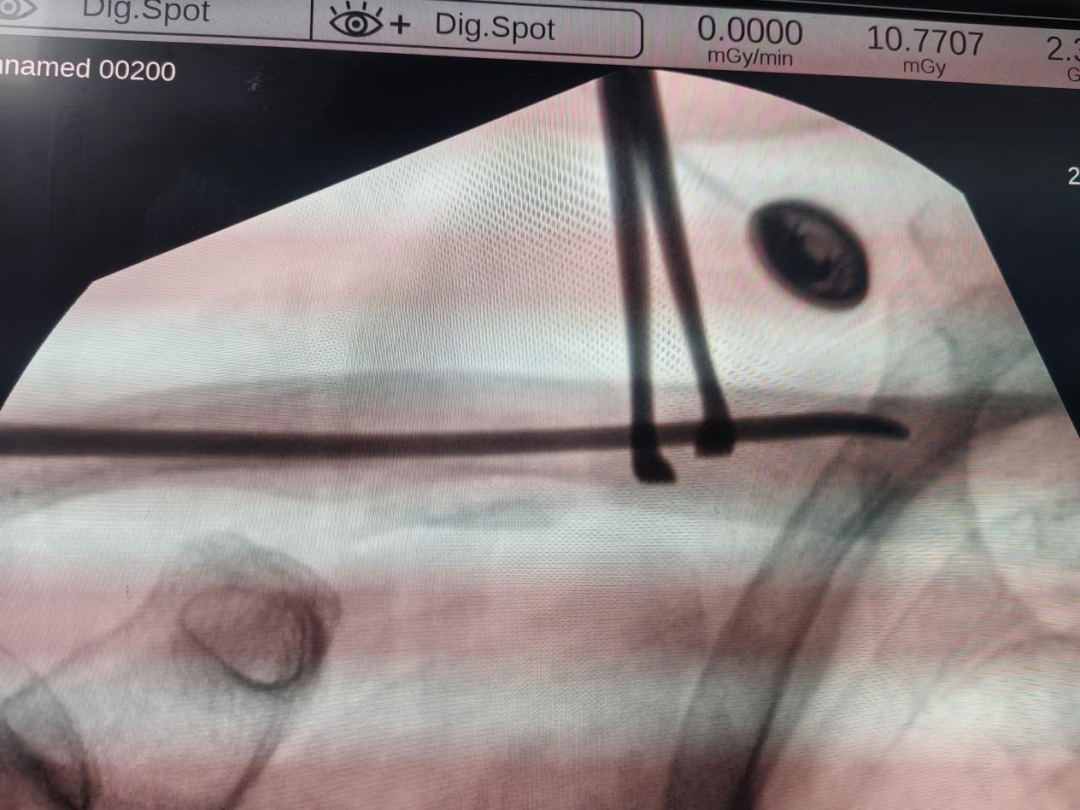

定“路线”:天玑机器人机械臂缓缓移动,精准标记定位点,C臂机快速捕捉影像并上传系统,自动规划出最优进针点和钉道;

做“小切口”:仅在锁骨远端开了个0.5cm的“绿豆”般微小切口,用开路锥钻开骨远端皮质,将3.0mm弹性髓内钉顺行插入锁骨髓腔——第一阶段骨折初步复位固定,顺利完成!